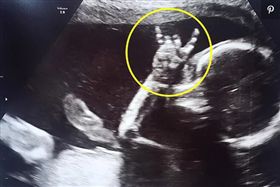

胎教聽音樂!寶寶超音波嗨比Rock

許多媽媽在懷孕時為了胎教都會給寶寶聽音樂,這對英國的...